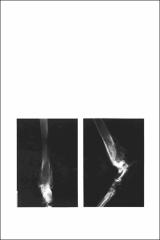

What's Your Radiographic Diagnosis?

A 14-month old intact female German Shepherd was presented with intermittent lameness of 14 days duration and swelling in the area of the distal left tibia. The area was tender and hot on palpation, there was disuse atrophy of the muscles of the left rear leg, and the popliteal lymph node of the left leg was enlarged.